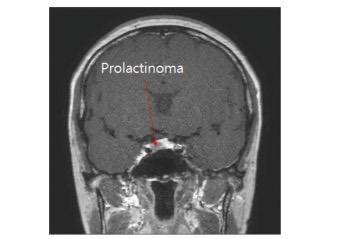

- 뇌하수체 선종

프로락틴 분비 선종(전체 뇌하수체 종양의 30~40%)이 가장 흔하며, 여성(20~40세)에서 미세선종(1cm 미만), 남성에서는 거대선종(1cm 이상)이 주로 발견됩니다[1][5].